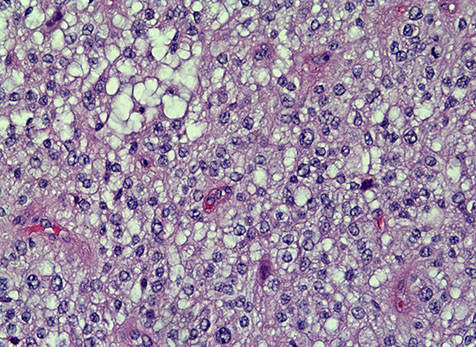

Glioblastoma multiforme (GBM)

More common in older pts (50's), involving the white matter

Imaging: heterogenous ring-enhancing mass with surrounding T2/FLAIR signal abnormality; if it crosses the midline, very likely to be a glioblastoma (butterfly lesion classic)

Micro shows an atypical infiltrative astrocytic glioma with frequent mits, pleomorphism, microvascular prolif and pseudopalisading necrosis

- either necrosis or microvasc prolif req'd for dx

- microvascular prolif is not an increase in the number of vessel spaces, but an increase in the thickness of the cellular coat of pericytes

-- thus to see microvasc prolif a smooth muscle actin (SMA) helps but a CD31 does not

Primary glioblastomas (de novo) occur in older pts, have EGFR amplification and/or PTEN mutations and have a very poor px

Secondary glioblastomas arise from a previous tumor that mutates and overexpresses p53, and has IDH1 mutations

- these have a slightly better px

- p53 usually seen in glial tumors (not as much in oligodendrogliomas) although p53 can be negative depending on the molecular pathway the tumor has taken

Genes: Isocitrate Dehydrogenase 1 mutation (IDH1): point mutation (R132H) in >1/2 of astrocytomas, oligodendrogliomas, and "mixed" gliomas (WHO Grades II-III)

- found in nearly all oligodendroglioma

- the mutation conveys a better px (wild type is worse)

-- mutation found in secondary GBM (since it is retained from its primary non-GBM tumor type) but NOT in primary GBM

- pts c hypermethylation of O(6)-methylguanine-DNA methyltransferase (MGMT) are more responsive to temozolomide and radiation tx

- higher expression of PD-L1 assoc c poor px [1]

- there are some treatments for blocking mutant IDH1 strains